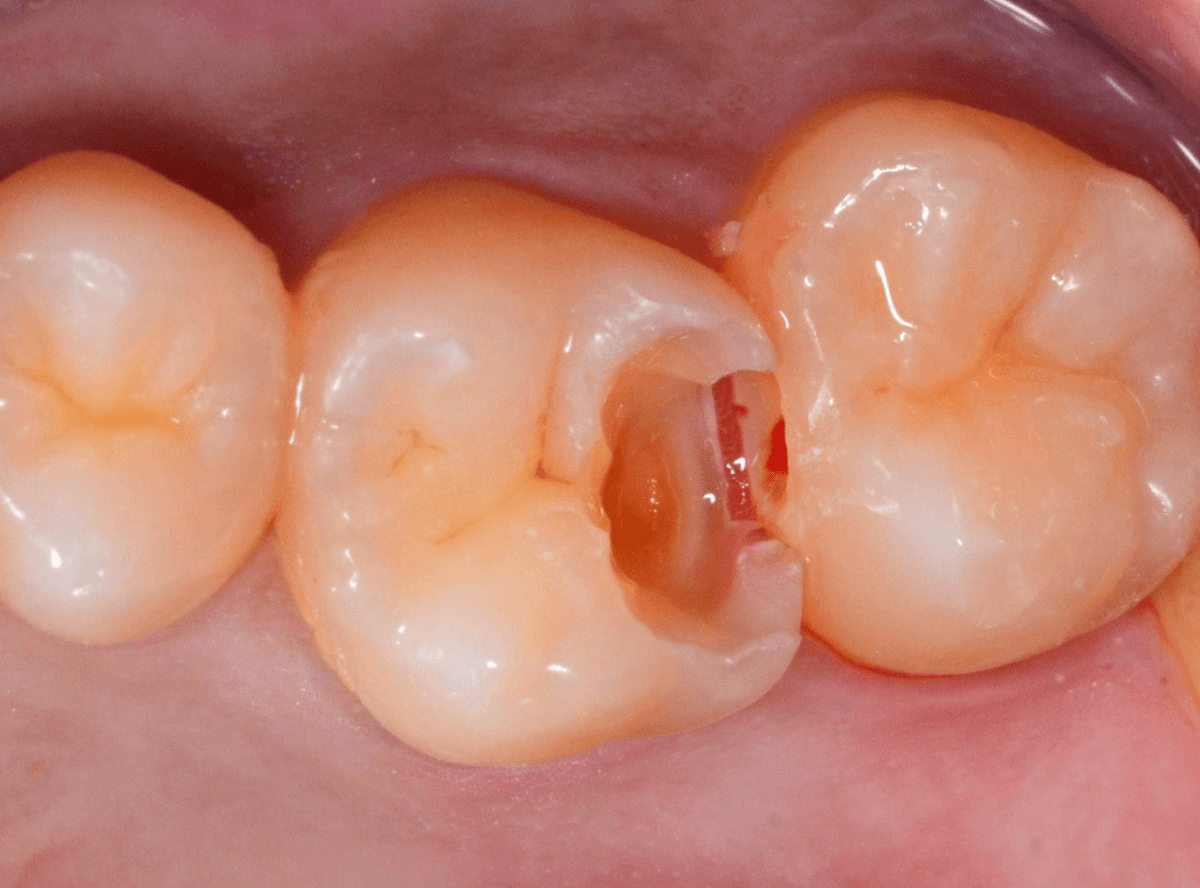

Case.19 神経まで達する大きな虫歯

「歯に違和感がある」という訴えで来院された患者さんです。

後ろの歯との間にぽっかり穴が開いているのがわかります。

このような場合、大抵は中で大きな虫歯になっています。

レントゲン写真で確認します。

青い部分が歯の神経、赤い部分が虫歯です。

レントゲン写真では、手前の歯との間も大きな虫歯になっているのがわかります。

そして、前後ともに神経まで達してしまっている虫歯に見えます。

治療を開始します。

少し削ったら、予想どおり大きな虫歯が出てきました。

虫歯が深いので、いつも以上に慎重に治療をすすめます。

赤くう蝕検知液で染まっている部分が虫歯です。

手前側は珍しく、レントゲン写真から予想される虫歯よりも小さかったです。

全ての虫歯を除去したところです。

やはり虫歯は大きく、歯の神経が一部露出する状況でした。

神経の中には血管もつまっていますので、出血するわけです。

神経を残せる可能性は半々といったところですが、神経を保護するお薬をつめた上にセメントで蓋をしました。

これでお痛みが出ないか、しばらく経過観察が必要です。